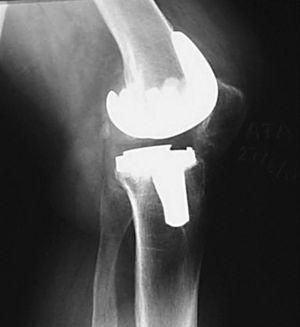

Se trata de una paciente de 69 años que fue diagnosticada de artrosis en la rodilla izquierda. En abril de 1994 se colocó una PTR Génesis I® (Smith and Nephew, Richards) preservando el ligamento cruzado posterior (LCP). Únicamente se cementó el platillo tibial, no protetizándose la rótula. Durante la cirugía el deslizamiento patelofemoral fue normal en todo el rango de movimiento. Trascurridas 48 horas tras la intervención, comenzó con un programa rehabilitador con artromotor. El arco de movilidad en los primeros tres meses era de 0-100°, la rodilla era indolora y estable, con un correcto alineamiento de los componentes. Al año de la intervención caminaba alrededor de dos horas sin bastones, pero precisaba de analgesia ocasional debido a un dolor patelofemoral con irradiación al hueco poplíteo y claudicación tras la sedestación («signo de la butaca»). El rango de movilidad empeoró a 0-80°. Estudios radiográficos con la proyección de Merchant mostraron una rótula centrada con un pequeño pinzamiento lateral y una ligera inclinación. Se indicó una protetización de la rótula y una operación de Ficat, pero fue desestimado por la enferma. Dos años y medio después la paciente caminaba sin bastones durante más de una hora por superficie llana, no podía bajar escalones ni siquiera de forma recíproca y se quejaba de rigidez de la rodilla al iniciar la deambulación. El dolor empeoró y la movilidad fue de 0-55°. Los estudios para detectar infección fueron negativos. Las radiografías seriadas mostraron una progresiva retracción del tendón rotuliano, llegando hasta el 25% y una rótula cada vez más descendida. Antes de la cirugía, la puntuación de la Sociedad Americana de Rodilla (KSS) era de 29 + 30, el polo distal de la rótula contactaba con el labio anterior del polietileno (fig. 1) y el arco de movilidad era 0-25°. El índice de Insall-Salvati era de 0,73, Blackburne de 0,69 y Caton de 0,69.

Figura 1. Retracción del tendón rotuliano y rótula baja.